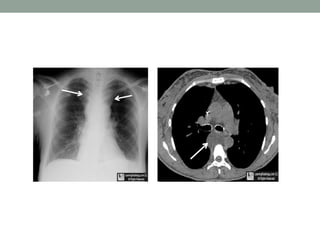

On the PA film there is a

lobulated paratracheal

stripe on the right.

On the lateral radiograph

there is a density overlying

the ascending aorta and

filling the retrosternal

space.

These findings indicate a

mass in the anterior as

well as in the middle

mediastinum.

The CT confirms the presence of lymphomas in both the

anterior and the middle mediastinum.